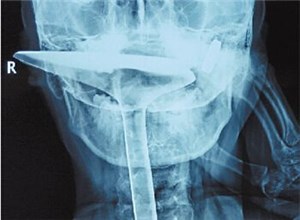

绍兴66岁大爷拿锅铲捅喉止痒 拔不出来被送医